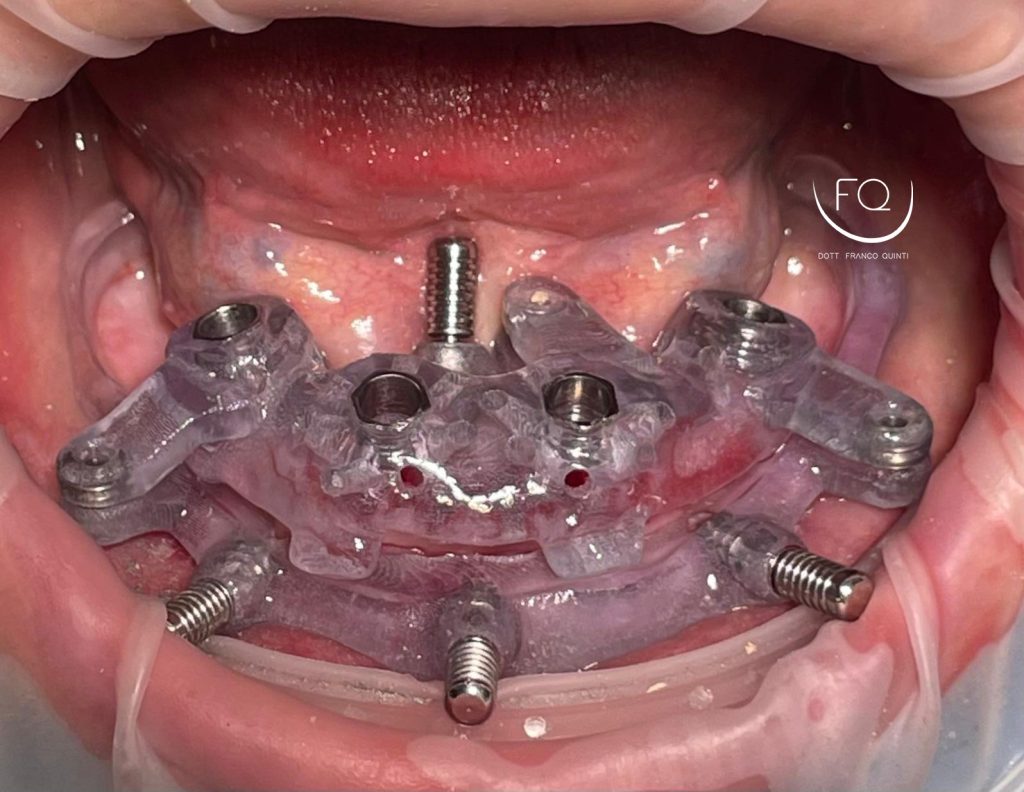

Oggi vi presento un caso di riabilitazione dell’arcata inferiore eseguito con l’utilizzo di dime scomponibili.

Il trattamento ha previsto l’inserimento di 4 impianti Prama Power di Sweden & Martina e la contestuale riabilitazione protesica provvisoria. Tra 3 mesi il caso verrà finalizzato con una protesi definitiva.